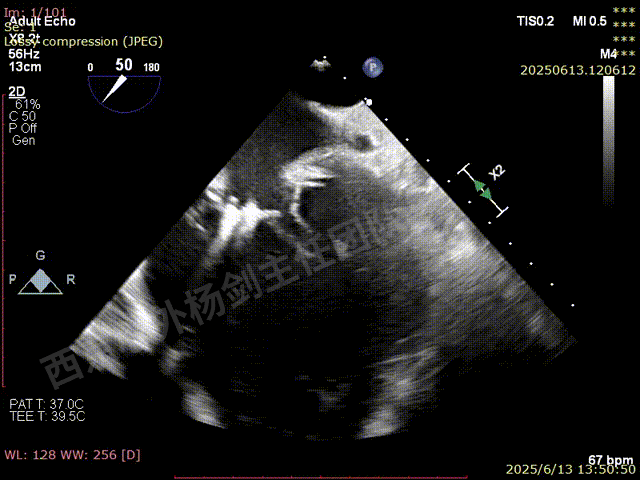

第二枚XT关闭后评估,trace

释放后评估,反流降至1+,组织桥稳定